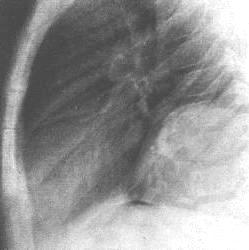

心包內惡性畸胎瘤X光圖早期病人無明顯臨床症狀,不易診斷。如出現胸部不適或心前區刺痛,心電圖僅提示心率異常無特異性。普通胸片檢查常因腫瘤與心臟影像重疊可造成漏診或誤診。近年來影像學發展迅速,現代化的高科技影像設備和技術已經成為心包內畸胎瘤診斷的主要檢查手段超聲心動描記或攝影心血管螢光電影照像術以及放射性核素掃描等綜合檢查,可以發現心包內腫塊的密實影像或回聲以及大量的心包腔積液。計算機中軸體層攝影(CT)對不同密度的組織如脂肪、水軟組織、骨骼的高解析度使心包內畸胎瘤的術前診斷成為可能磁共振成像(MRI),利用心血管中血液的流空效應也對本病的診斷很有意義。